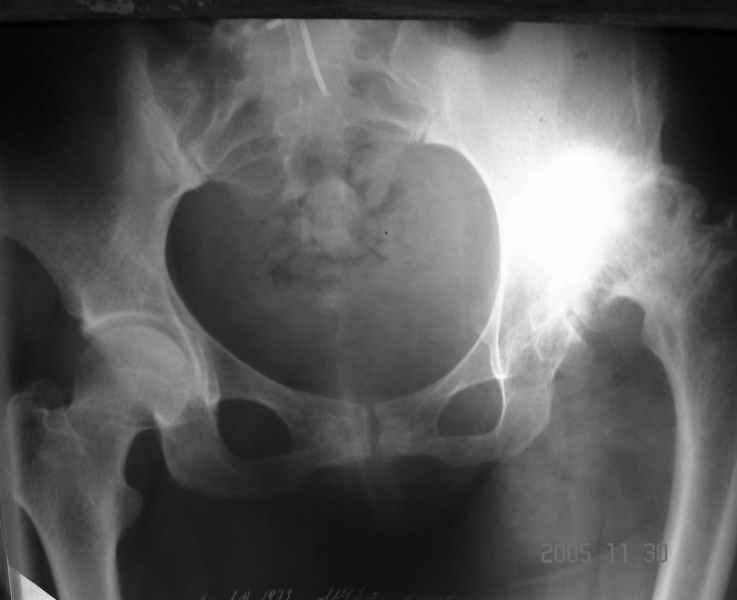

Аксиальный Р-снимок

Шишков Алексей (ГКБ№13 г. Уфа)

Вы вполне можете обойтись стандартной клиновидной ножкой, определенные сложности будут в установке вертлужного компонента. Если есть вопросы, не стесняйтесь, спрашивайте.

Аксиальная рентгенограмма подтверждает, что Вы имеете дело со стандартным случаем диспластического коксартроза. Смею присоединиться к мнениям коллег

по поводу бесцементного протезирования сустава. Особого затруднения у опытного специалиста этот случай не вызовет. Возможно протребуется тенотомия

приводящих мышц и некоторый релиз места присоединения ягодичных мышц в области вершины большого вертела. Это позволит одномоментно удлиненить конечность без опасения неврологических осложнений. АИФ.